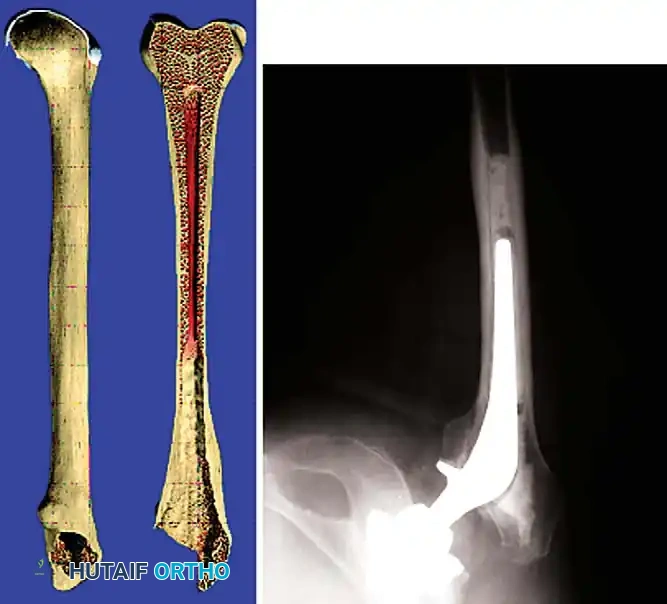

Femoral Reconstruction

Femoral bone loss dictates stem selection. The fundamental biomechanical principle of femoral revision is to achieve rigid fixation in healthy, diaphyseal bone, bypassing the proximal deficiency by a minimum of two cortical diameters (typically 4-6 cm).

Implant Options:

1. Fully Porous-Coated Cylindrical Stems: Excellent long-term survivorship in Type I and II femoral defects. They rely on extensive diaphyseal scratch fit.

2. Modular Fluted Tapered Stems: The modern workhorse for severe (Type III and IV) defects. The flutes provide rotational stability, while the 2-to-3 degree taper achieves axial stability via three-point fixation in the diaphysis. Modularity allows independent adjustment of version, offset, and leg length after the distal stem is rigidly seated.

Pitfall: When seating a diaphyseal-engaging stem, prophylactic cerclage cabling of the distal femur is highly recommended to prevent catastrophic intraoperative splitting of the diaphysis during final impaction.